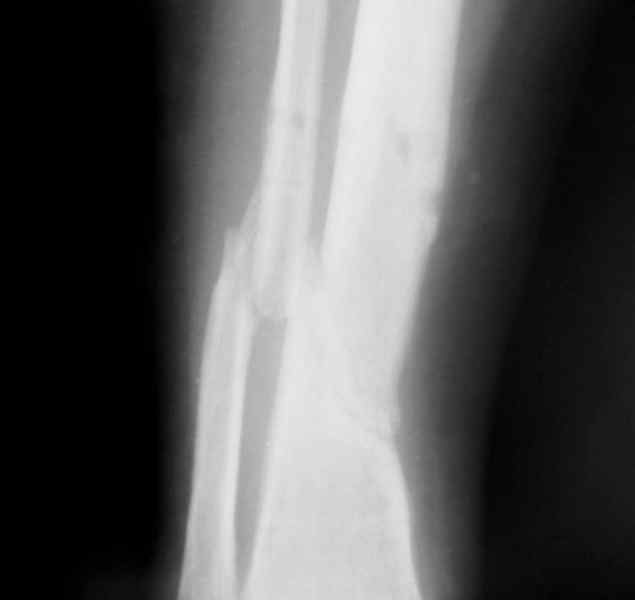

Больная 54 года, 5 м. назад открытый оскольчатый перелом 2-3 тип, Первично ЧКДО, открытое ведение раны, при этапных некрэктомия " ушел" осколок внутренней стенки б/бецовой кости, 7 сутки пластика м/тканями ,вторичные швы.

Контакт отломков только по спирали наружной стенки,заживление раны полное, на 3-4 месяце ЧКДО воздействие на регенерацию микродистрациями , 5 месяц снят аппарат по причине нестабильности и реакции м/тканей. В данный момент проблем с тканями нет, на Р-граммах псевдоартроз, клинически подвижность,больная ходит в ортезе с дозированной нагрузкой.Местно рубцовый процесс 3х5 в зоне перелома.

Вы имеете дело не с псевдоартрозом, а с замедленно срастающимся переломом.

Будьте добры послать снимки до операции . а также после операции, на которых видна компановка аппарата Илизарова. Кстати на представвленных рентгенограммах в аппарате есть спица с напайкой, проведённая проксимально перелома через обе кости... Если можно, объясните необходимость такого проведения.